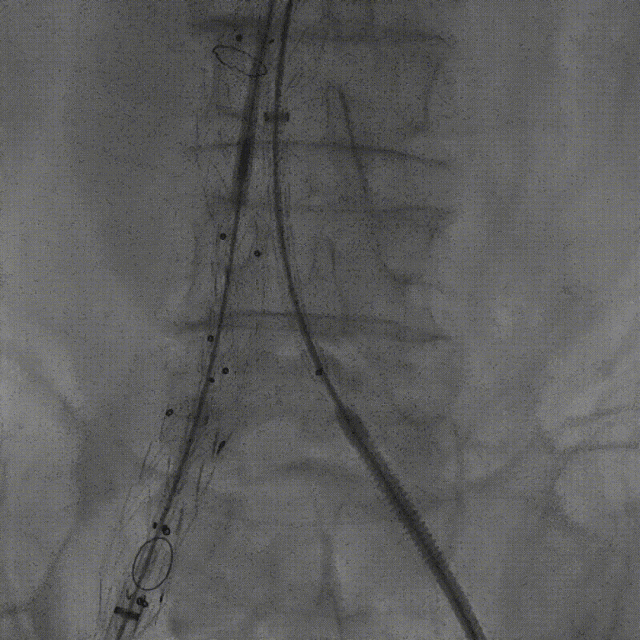

案例三(梯形瘤颈):3年前肾结石,在治疗复查过程中发现腹主动脉瘤。

案例四(梯形瘤颈):因下肢髋部疼痛行腰椎检查时发现腹主动脉瘤,进一步CTA认证确诊为腹主动脉瘤。

案例五:查体发现腹主动脉,行CTA确认腹主动脉瘤伴血栓形成。

截至目前,采用Reverse技术处理不良瘤颈的初步经验(21例)显示,术中发生明显I型内漏仅3例,其中2例经弹簧圈栓塞处理,1例在随访中自行消失。这表明Reverse技术在处理不良瘤颈时,是一种安全、有效且能显著减少内漏发生的手段。